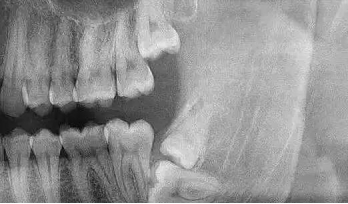

阻生牙(impacted teeth)是指部分萌出或完全不能萌出,且以后也不会自行萌出的牙。好发部位为下颌第三磨牙、上颌第三磨牙及上颌尖牙,其中阻生第三磨牙也叫做阻生智齿。

5、邻牙及支持组织的吸收:当阻生的智齿萌出过程中受阻于第二磨牙时,会引发第二磨牙牙根牙根逐渐吸收,严重者可使下颌第二磨牙远中牙根完全吸收,致第二磨牙松动、疼痛,常常食物嵌塞发生慢性牙周炎,也会造成牙槽骨的炎症性吸收,使第二磨牙反复肿痛。